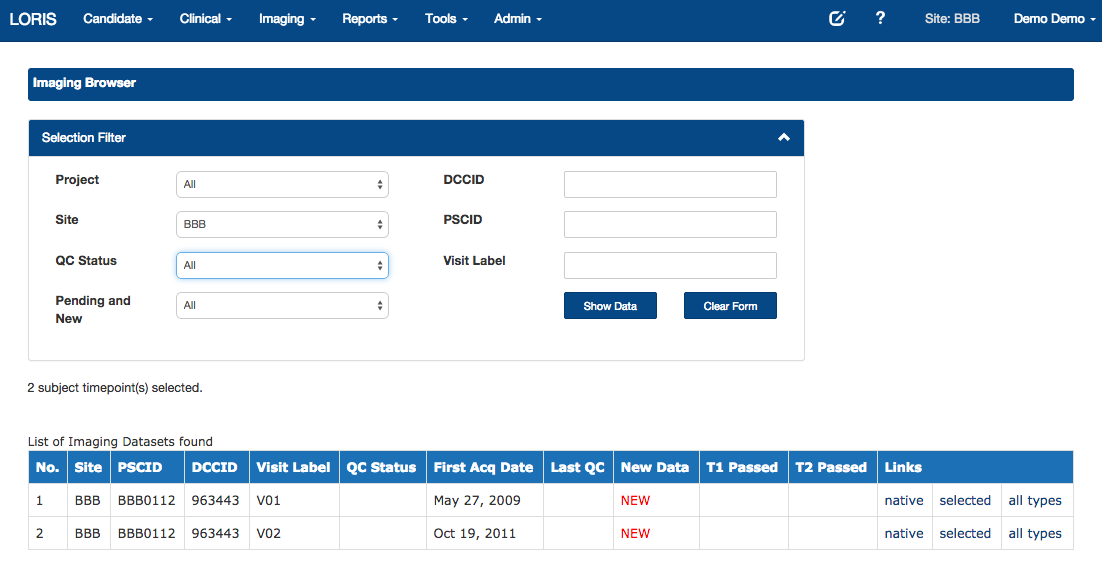

Imaging Browser

Imaging Quality Control